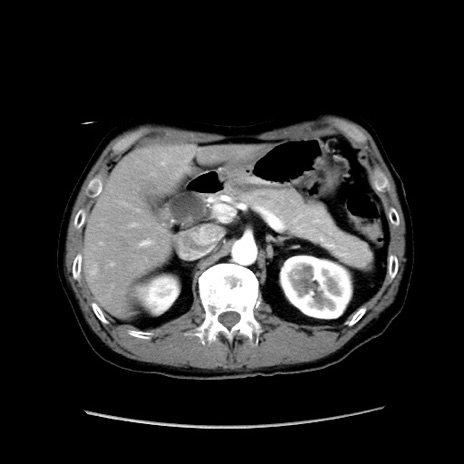

症例37(横断像)

【症例】40歳代 男性

【主訴】腹痛

【現病歴】4時間ほど前に電車に乗車中に臍部上より腹痛出現。徐々に増悪し起立困難となり、救急外来受診。生ものは数日食べていない。今朝お雑煮を食べた。

【身体所見】BT 36.8℃、BP 117/84mmHg、HR 91/min、SpO2 97%、苦悶様、腹部:臍上部広範囲圧痛あり、反跳痛±

【データ】WBC 8100、CRP 0.03